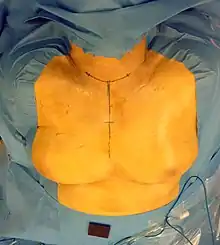

Abord chirurgical

La thyroïde est généralement abordée par une cervicotomie médiane, qui peut être élargie latéralement en cervicotomie en U s'il existe une nécessité de curage ganglionnaire cervical. En cas de volumineux goitre plongeant, un refend cutané en Y en regard de l'extrémité crâniale du sternum sera souvent pratiqué. Au maximum, une simple manubriotomie (on parle alors de cervicomanubriotomie) ou une sternotomie médiane pourra être pratiquée.